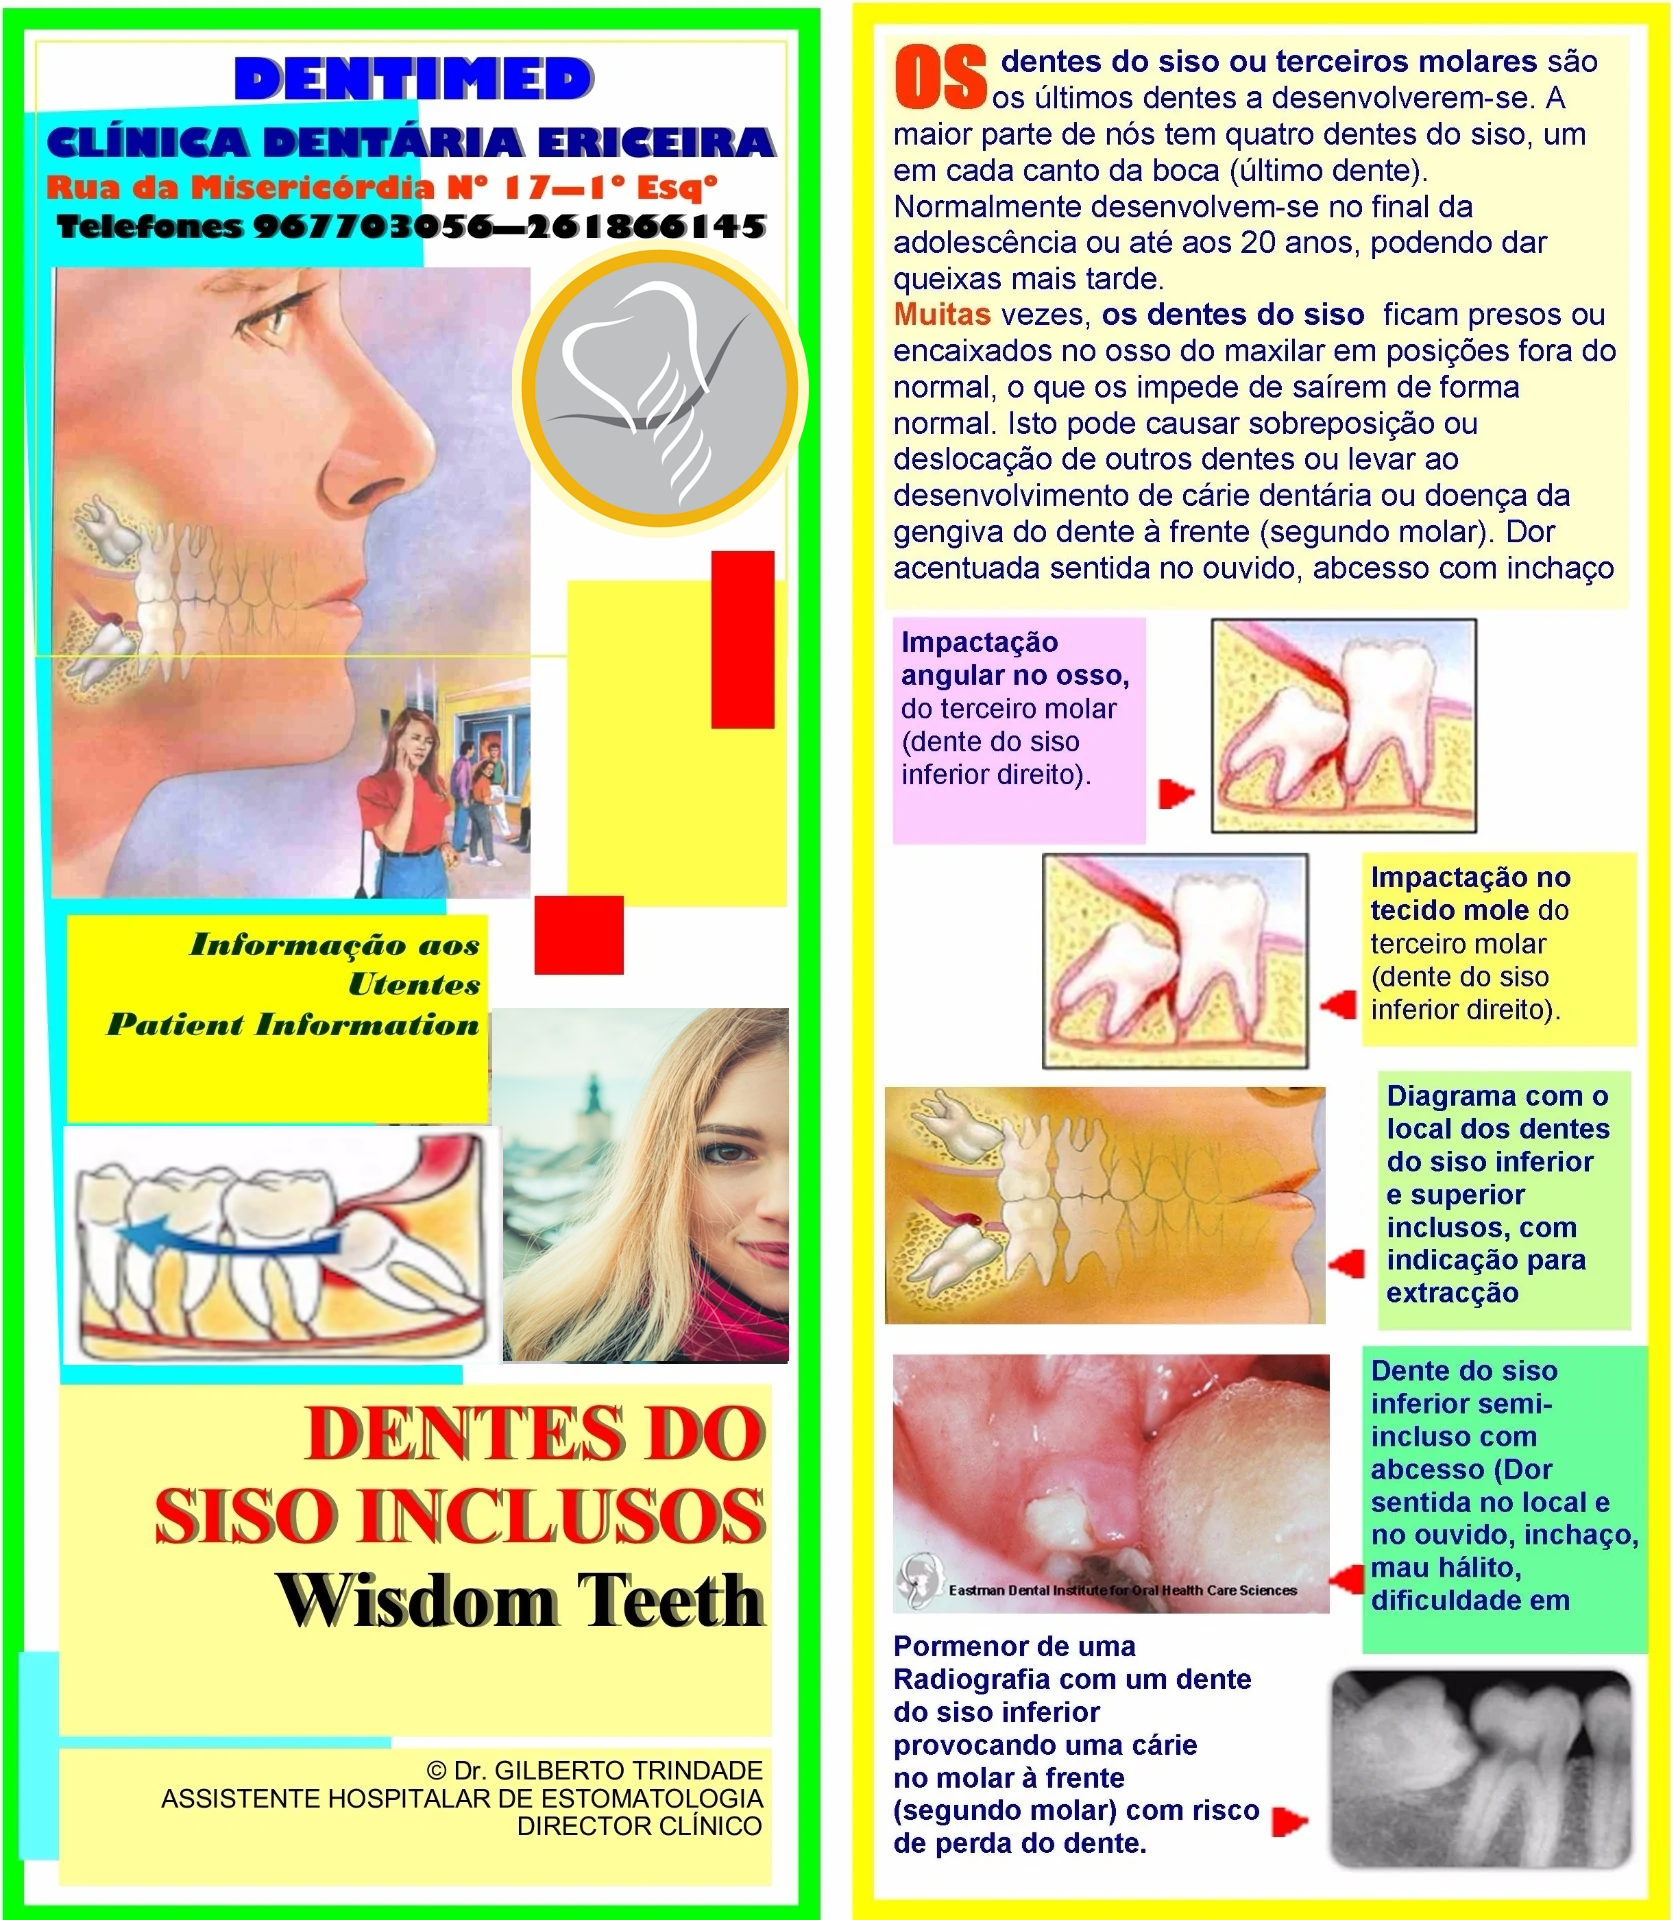

Extração de Sisos Inclusos

Os dentes do siso ou 3ºs molares são os últimos dentes a erupcionar ("nascer"). A maior parte de nós tem 4 dentes do siso, um em cada canto da boca (último dente). Normalmente desenvolvem-se no final da adolescência ou até aos 20 anos, podendo dar queixas mais tarde. Muitas vezes, os dentes do siso ficam presos ou encaixados no osso do maxilar em posições fora do normal, o que os impede de saírem de forma normal. Isto pode causar sobreposição ou deslocação de outros dentes ou levar ao desenvolvimento de cárie dentária ou doença da gengiva do dente à frente (segundo molar); dor acentuada sentida no ouvido, abcesso com inchaço da face e dificuldade em mastigar são frequentes. Na maior parte dos casos, é recomendado extrair os dentes do siso inclusos. A cirurgia para remoção do terceiro molar ou dente do siso pode ser realizada na DENTIMED Clínica Dentária Ericeira. É necessário avaliar previamente o seu estado de saúde, podendo ser necessário efectuar análises e uma Radiografia. Para isso poderá pedir para ser observado num dos Períodos em que damos Consulta, sem marcação. Aí será então marcada a cirurgia. No dia da cirurgia não venha sem comer. Tome os medicamentos receitados. Siga os outros conselhos que lhe forem dados.